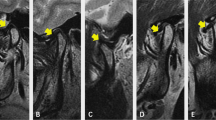

Kim YK, Yun PY, Ahn JY, Kim JW, Kim SG (2009) Changes in the temporomandibular joint disc position after orthognathic surgery. Oral Surg Oral Med Oral Pathol Oral Radiol Endod 108:15–21. https://doi.org/10.1016/j.tripleo.2009.02.005

Ueki K, Marukawa K, Nakagawa K, Yamamoto E (2002) Condylar and temporomandibular joint disk positions after mandibular osteotomy for prognathism. J Oral Maxillofac Surg 60:1424–1432. https://doi.org/10.1053/joms.2002.36098